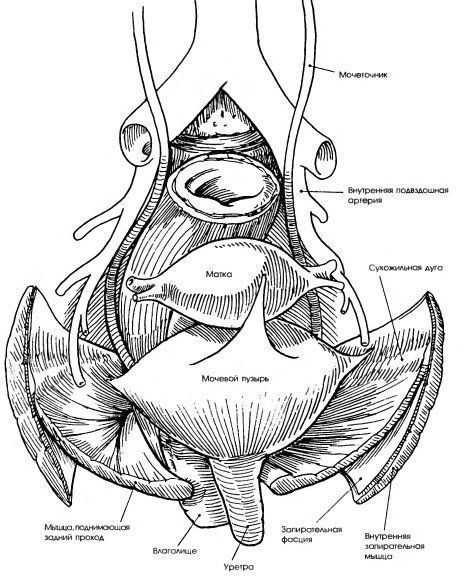

Анатомия малого таза: детальные схемы и изображения